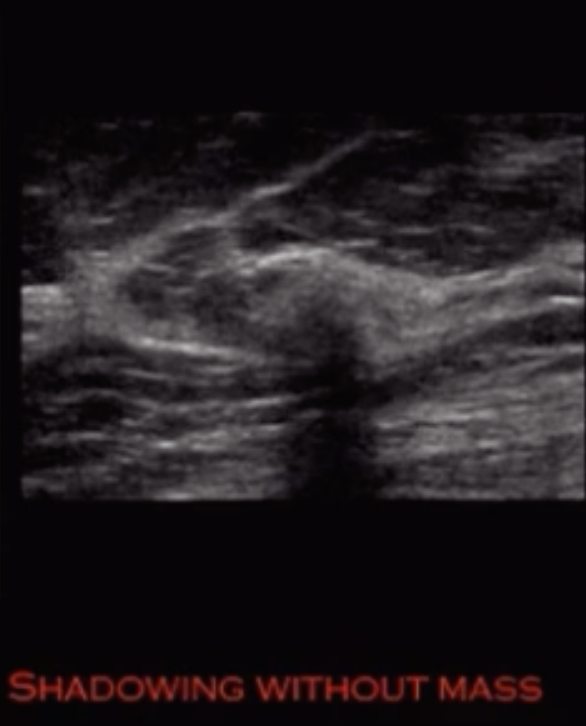

• Shadowing on US without evidence of definitive mass

• Dark star appearance

• Architectural distortion without definitive central mass on MG